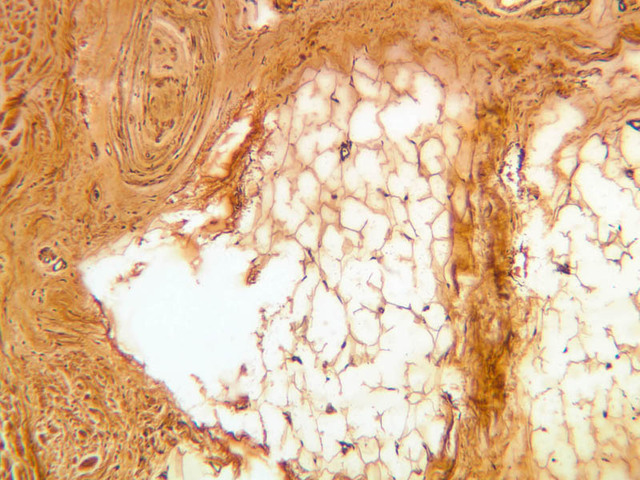

In some dermal papillae that project up into the epidermis can be found examples of Meissner's corpuscles, which are sensory receptors for light touch (slide A-57, fingertip, Sevier Ag [10x, 20x, 40x-labeled] [10x, 20x, 40x]; A-50, fingertip, H&E [2.5x, 10x, 20x, 40x, 40x] [10x, 20x, 40x] [20x, 40x]). The corpuscles tend to have an oval or conical shape. Look for one of these receptors, particularly in hairless skin.

Deep pressure receptors known as Pacinian corpuscles also occur in the skin, as well as other sites (A-57 [2.5x-labeled, 10x, 20x, 40x-labeled] [2.5x, 10x, 20x, 40x-labeled]; A-50 [2.5x, 10x, 20x, 40x]). The sectioned appearance of the Pacinian corpuscle resembles a slice of onion, consisting of numerous concentric layers of tissue. Nerve endings generally thought to be responsible for pain sensation occur as bare fibers within the epithelial layers of skin epidermis, but these are not apparent in routinely stained sections (A-57, fingertip, Sevier Ag [10x, 20x, 40x] [10x, 20x, 40x] [20x, 40x] [20x, 40x]).